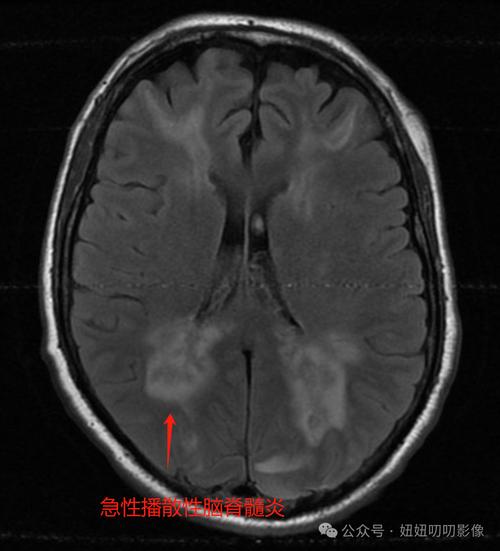

急性播散性脑脊髓炎:

(图片来源网络,侵删)- 性质:这是一种单次、急性的免疫攻击,通常发生在病毒或细菌感染(如感冒、出水痘、接种疫苗后)后的1-2周内。

- 特点:免疫系统被“激活”后,错误地攻击了自身的髓鞘,造成一次性的损伤。

- 预后:绝大多数预后良好,经过急性期的激素冲击等治疗,大部分孩子可以完全康复或基本康复,不留后遗症或仅有轻微后遗症,它更像是一次“免疫风暴”后的修复过程。